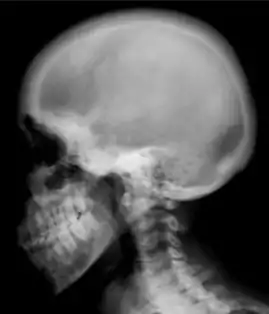

Renal osteodystrophy is usually diagnosed after treatment for end-stage kidney disease begins; however the CKD-MBD starts early in the course of CKD.[1][6] In advanced stages, blood tests will indicate decreased calcium and calcitriol (vitamin D) and increased phosphate, and parathyroid hormone levels. In earlier stages, serum calcium, phosphate levels are normal at the expense of high parathyroid hormone and fibroblast growth factor-23 levels. X-rays will also show bone features of renal osteodystrophy (subperiostic bone resorption, chondrocalcinosis at the knees and pubic symphysis, osteopenia and bone fractures) but may be difficult to differentiate from other conditions. Since the diagnosis of these bone abnormalities cannot be obtained correctly by current clinical, biochemical, and imaging methods (including measurement of bone-mineral density), bone biopsy has been, and still remains, the gold standard analysis for assessing the exact type of renal osteodystrophy.[6][15]